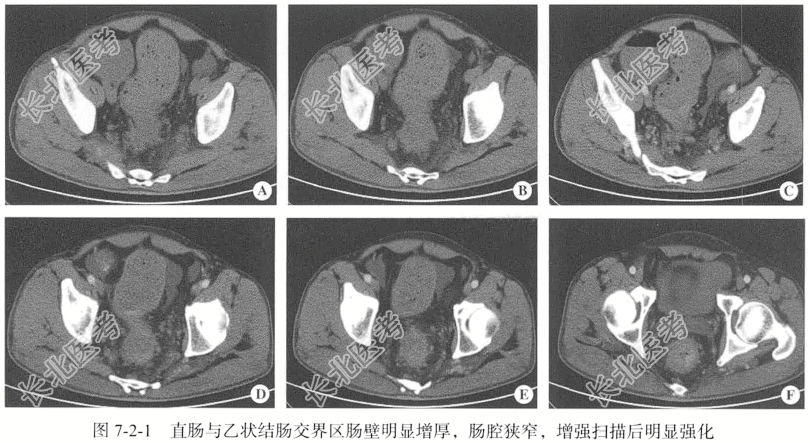

【影像图片】见图7-2-1。

【手术所见】腹腔内少量淡黄色腹水,肿瘤位于直肠,周围多发肿大淋巴结侵犯盆壁,盆壁呈实性固定。

【病理所见】肉眼所见(直肠)小渣组织4块,呈淡粉色,质中(图7-2-2)。免疫组化结果:AE1/AE3(+),CDX2(+),Ki-67(80%+),Syn(+),CgA(+)。

【病理诊断】神经内分泌癌。